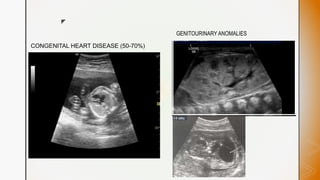

CONGENITAL HEART DISEASE (50-70%)

GENITOURINARY ANOMALIES